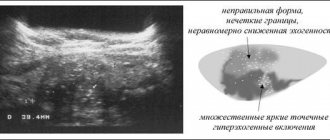

Это генетическая патология характеризуется ростом кист в полости почки. Они нарушают основные функции, а визуально орган становится похожим на гроздь винограда. В результате разрастания ткани почка увеличивается в размерах, что вызывает неприятные, а порой и болезненные симптомы.

При заболевании почек в обеих частях органа образуются многочисленные заполненные жидкостью кисты, которые со временем увеличиваются в размере. Болезнь влечёт за собой нарушение нормальной работоспособности органа, приводит к терминальной почечной недостаточности и необходимости пересадки почки.